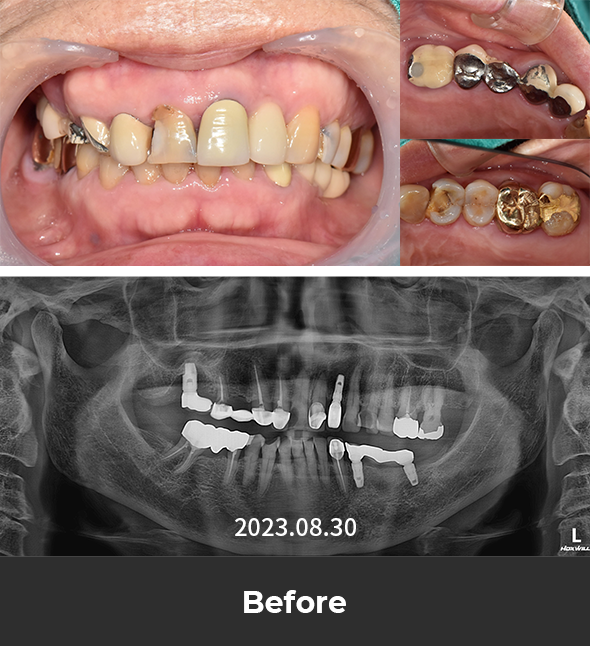

· 네비게이션 임플란트 / 상하악 식립 case

치료 후 사진

3~4개월 전 타치과에서 시술 마무리하였지만

불편한 곳이 또생겨 검진 진행한 케이스

하악 발치 진행 후 임시틀니 사용,

이후 임플란트 식립 2달 뒤 체결하며 최종 부분 틀니 완성

*환자분 비용부담 보험임플란트 2개,

보험틀니 활용하여 적은 비용으로 하악치료 완성